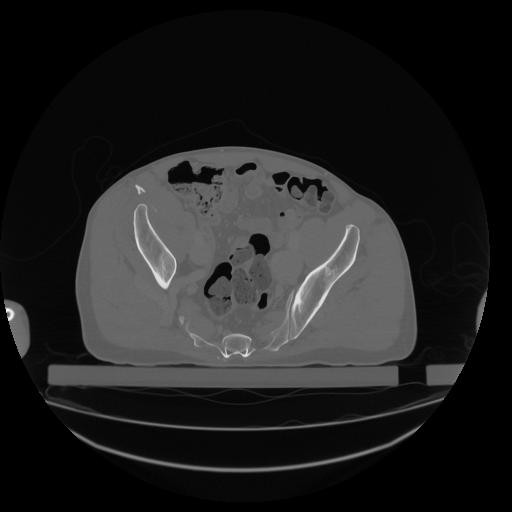

34 CUERPO,CE,Vol,1.0,CUERPO,,